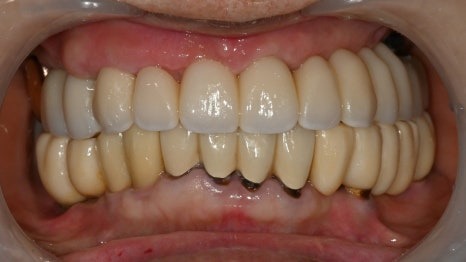

2개월 후,

잘 굳어진 임플란트 뿌리에

보철물을 만들기 위해

구강 내 스캔을 진행하였습니다.

병원내에 있는

디지털 기공센터에서

CAD/CAM 밀링기계를 이용하여

치아를 제작하였고,

전체 임플란트 임에도

정확하게 잘 맞아서

아주 만족해하셨습니다.

수술 후 2개월, 최종치아 장착

걱정하셨던 것보다 훨씬

수월한 치료 과정과

짧은 치료 기간으로

너무 만족해하셨던 케이스입니다.